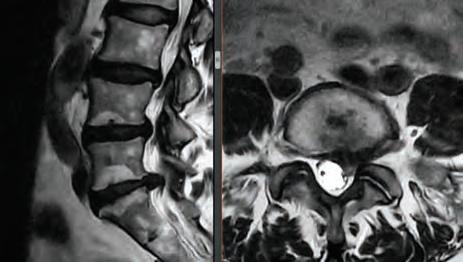

COLLIN COUNTY • 5 15 A Primer on Probate 18 Strokes, Heart Attacks, and Vision Loss 21 Depression and Hearing Loss 31 A Meaningful and Appropriate Funeral 36 Which Care Option Do I Need? 37 Experiencing Neck or Back Pain? CONTENTS FOLLOW US ON SOCIAL MEDIA @ LivingWellmag @ LivingWellmags @ LivingWellmags @ LivingWellmagaz MAY/JUNE 2023 More Inside SHANIA TWAIN QUEEN OF COUNTRY, RESILIENCE, AND REINVENTION SECRETS TO HAPPY MARRIAGE QUOTES FROM LONG-MARRIED COUPLES PRIMER ON PROBATE Stephen Courtney,P.MD ADVANCED SPINE CENTER Visit LivingWellMag.com for a free digital subscription. 44 24 8 FEATURES AND MUCH MORE... 8 Dr. Stephen P. Courtney Advanced Spine Center 24 Shania Twain Queen of Country, Resilience, and Reinvention 44 Secrets to a Happy Marriage Quotes From Long-Married Couples

Led by Dr. Courtney, the skilled team at Advanced Spine Center cares for patients with neck and back pain using a wide array of the most state-of-the-art tools and techniques—from conservative physical therapy and injection therapy—to advanced pain manage-

ment, as well as surgical intervention. We employ the latest in minimally invasive spine surgeries, in addition to cutting-edge replacement technology. Incorporating both high tech and high touch, we get our valued patients back to their lives so they can enjoy all the activities they love.